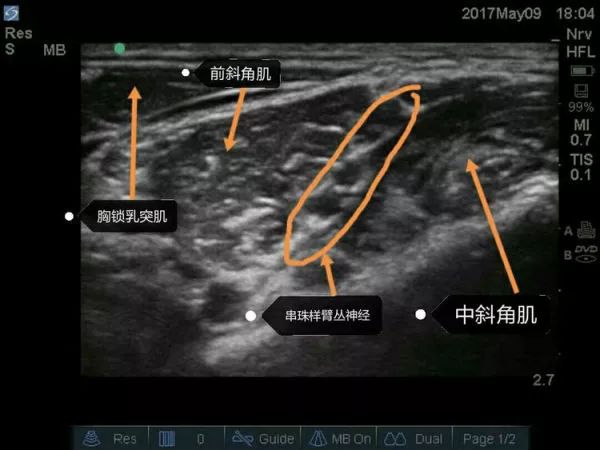

超声下肌间沟水平臂丛的走行图像,上面是胸锁乳突肌,左右是前、中斜角肌。肌间沟水平下可清楚看到呈串珠样的臂丛,C5、C6、C7等。请大家关注下,有的时候能看见5个“串珠”,不要以为是臂丛的5个根即C5、C6、C7、C8、T1,肌间沟往往是在颈椎7水平,怎么可能看到C8、T1,其实就是C5、C6、C7,那为什么是5个“串珠”?因为C6及C7在肌间沟水平已经分出2根,要避免在这2根汇合处之间穿刺而造成C6及C7的神经损伤。